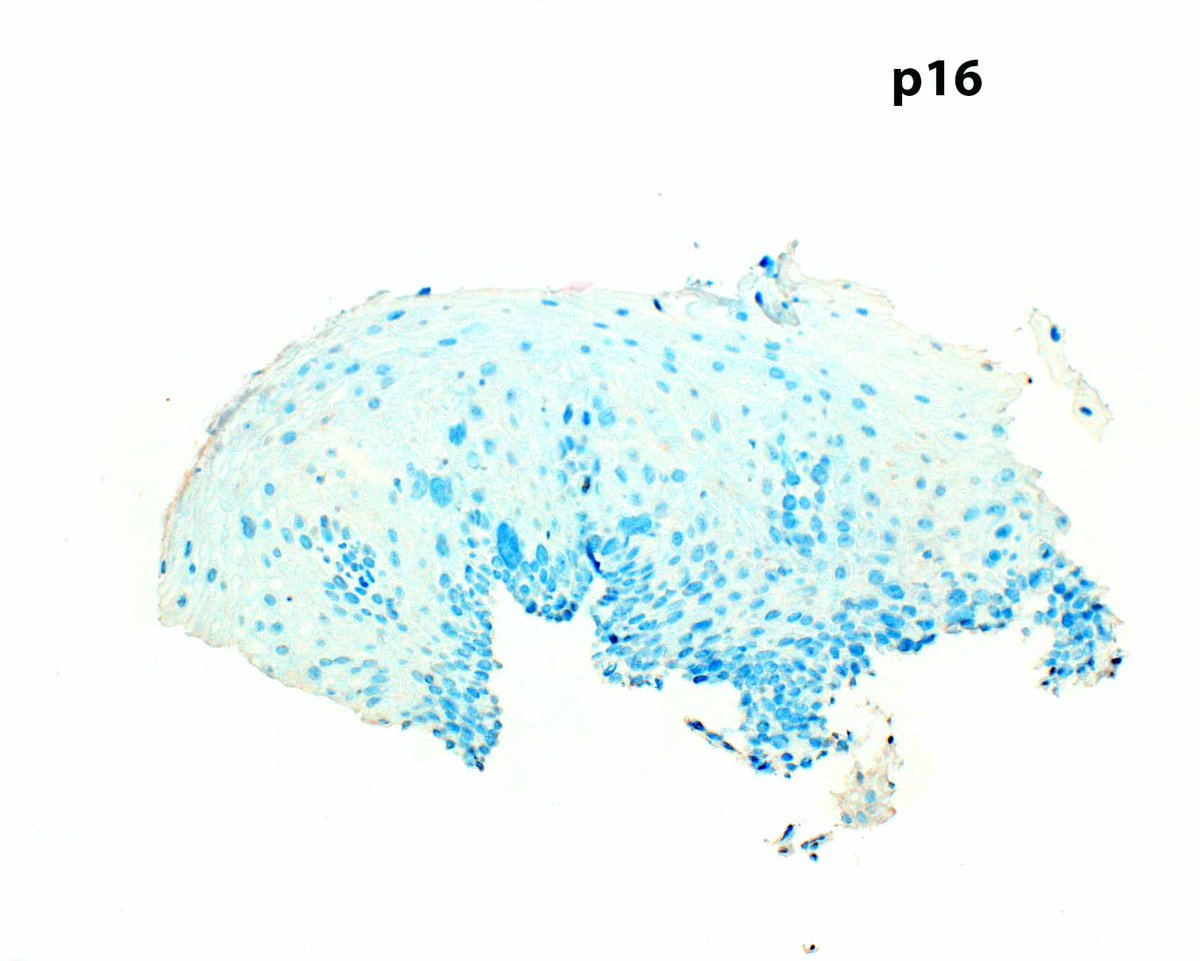

p53 IHC can help confirm a diagnosis of esophageal squamous dysplasia. In occasional HPV-associated cases, p16 staining is strongly reactive. This example is probably driven by a TP53 mutation. Don't expect the full thickness staining typical of glandular dysplasia.

LizMontgomeryMD's tweet image. p53 IHC can help confirm a diagnosis of esophageal squamous dysplasia.  In occasional HPV-associated cases, p16 staining is strongly reactive. This example is probably driven by a TP53 mutation.   Don't expect the full thickness staining typical of glandular dysplasia.